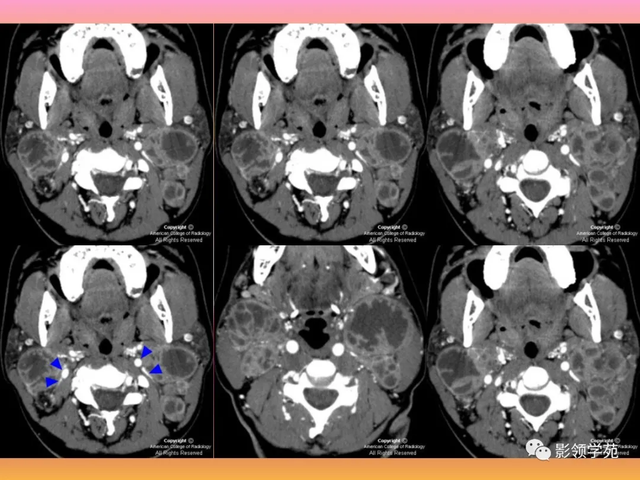

部门腮腺肿瘤的特点:

囊肿、脂肪瘤:低密度

海绵状血管瘤:强化显著

混淆瘤:钙化、囊变

腺淋巴瘤:MF,浅叶后下极,双侧多中央

腺样囊性癌:嗜神经生长(面瘫)。

病例1:男性, 41岁,因“发现右耳垂下肿物1月余”:

病理:混淆瘤

病例2:女,30岁,发现右耳垂下肿物9月

病例3:男性,68岁,因“发现右耳垂下肿物30余年”:

病理:腺淋巴瘤

病例4:男性,81岁,因发现右耳下肿物10年余,举行 性增大2年: